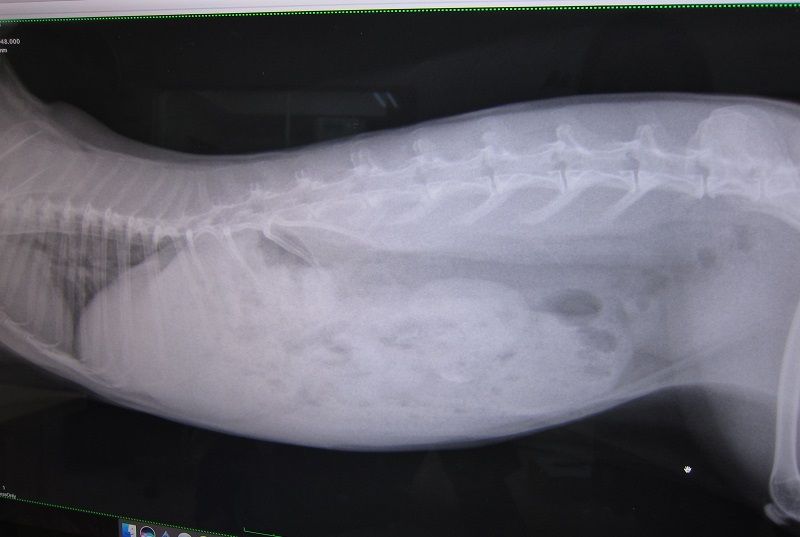

昨夜からの流れを話しし、診察、レントゲン

閉塞所見はありません

もちろん心臓も小さくなってないし

若干のガスはあれど、強いて指摘するならばレベル

で、ちゃんと出番待ちしとる(。・m・)

いつも感心するウンコ影“〆( ̄▽ ̄*)

と、胃腸に大きな問題はなさげだったのだが…

脂肪、すご過ぎやん…( ̄ェ ̄;)

前回との比較…